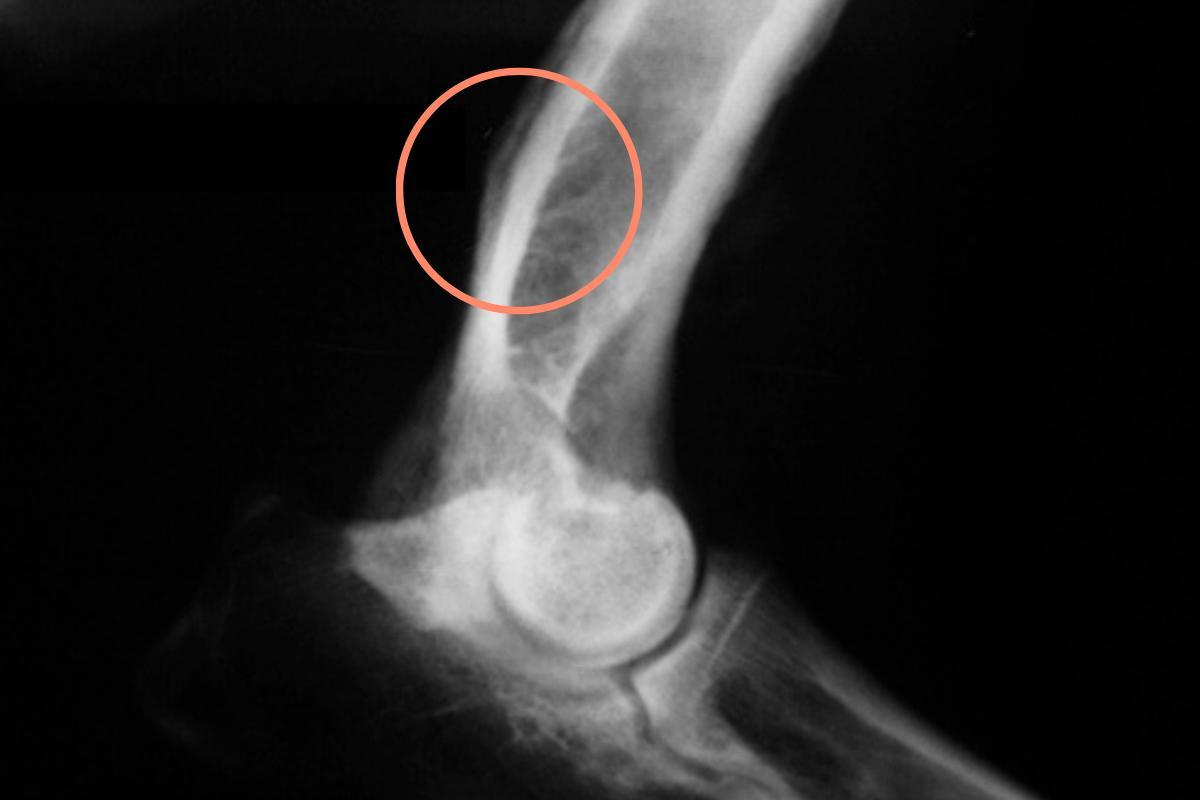

- Radiografia: lesões com margens irregulares e mal definidas, especialmente quando aparecem nos locais mais frequentes deste tumor, nos fazem suspeitar da existência do osteossarcoma canino. Além disso, as fraturas podem às vezes ser vistas na radiografia, pois uma pequena porcentagem de cães com osteossarcoma pode ter fraturas patológicas, ou seja, fraturas resultantes de danos ósseos causados pelo tumor. Vale mencionar que os exames de imagem permitem um diagnóstico presuntivo, mas para se chegar a um diagnóstico definitivo são necessários os seguintes exames:

- A localização anatômica também influencia o prognóstico do animal. Em particular, os tumores localizados no nível do úmero têm um prognóstico pior. Em contraste, os osteossarcomas localizados distalmente ao cotovelo e ao joelho (ou seja, aqueles na extremidade dos membros) estão associados a uma sobrevivência mais longa, de cerca de 465 dias, em média.